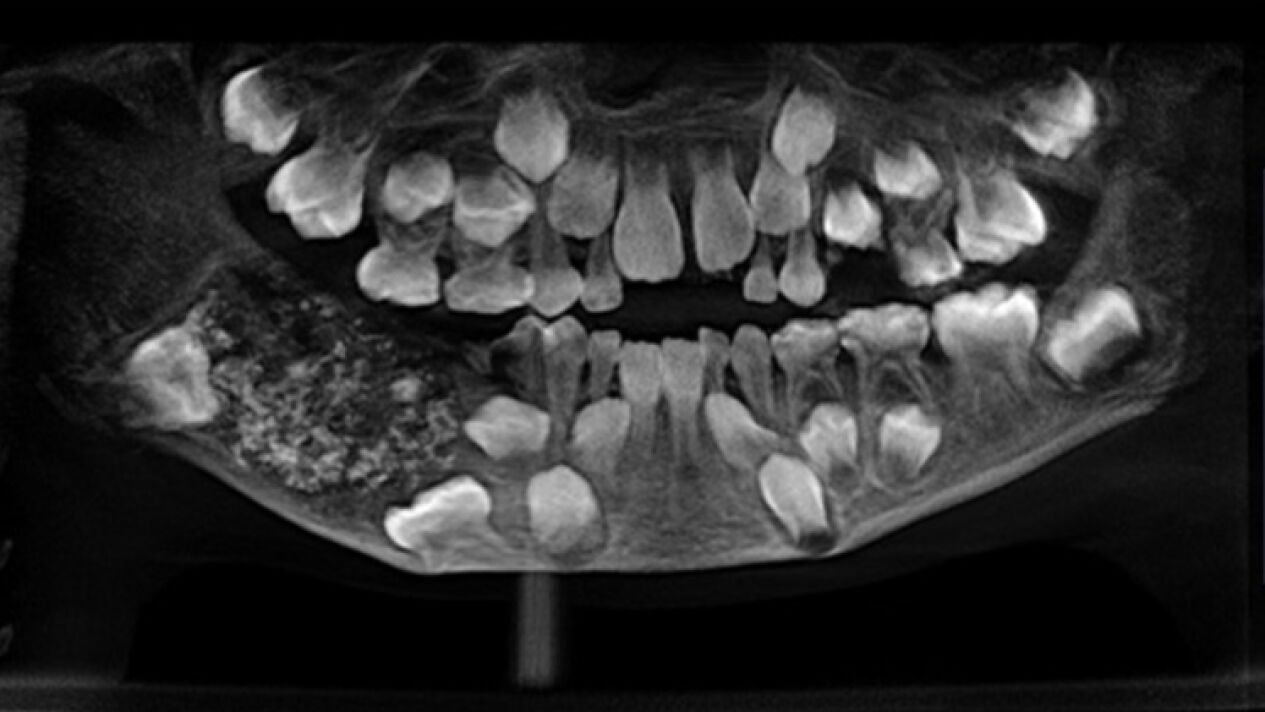

Un niño de 7 años ha sido intervenido durante cinco horas en el Hospital de la Universidad de Saveetha (India), una operación en la que le extrajeron la friolera de 526 dientes de su boca.

P. Ravindran llevaba arrastrando un fuerte dolor en su mandíbula desde los 3 años, llegando al centro médico con una importante hinchazón. Le realizaron diversas pruebas, tras las que llegaron a la conclusión de que tenía varias estructuras duras dentro de su mandíbula.

"Abrimos la mandíbula después de administrar anestesia general y vimos una bolsa dentro que pesaba alrededor de 200 gramos. Fue cuidadosamente removido y luego se encontró que contenía 526 dientes", explica P. Senthilnathan, profesor del Departamento de Cirugía Oral y Maxilofacial del Hospital.

'Odontoma compuesto' es el nombre que ha recibido esta peculiar dolencia, cuyo origen podría ser genética o ambiental, como reconocía el doctor Pratibha Ramani, profesor y jefe del Departamento de Patología Oral y Maxilofacial.